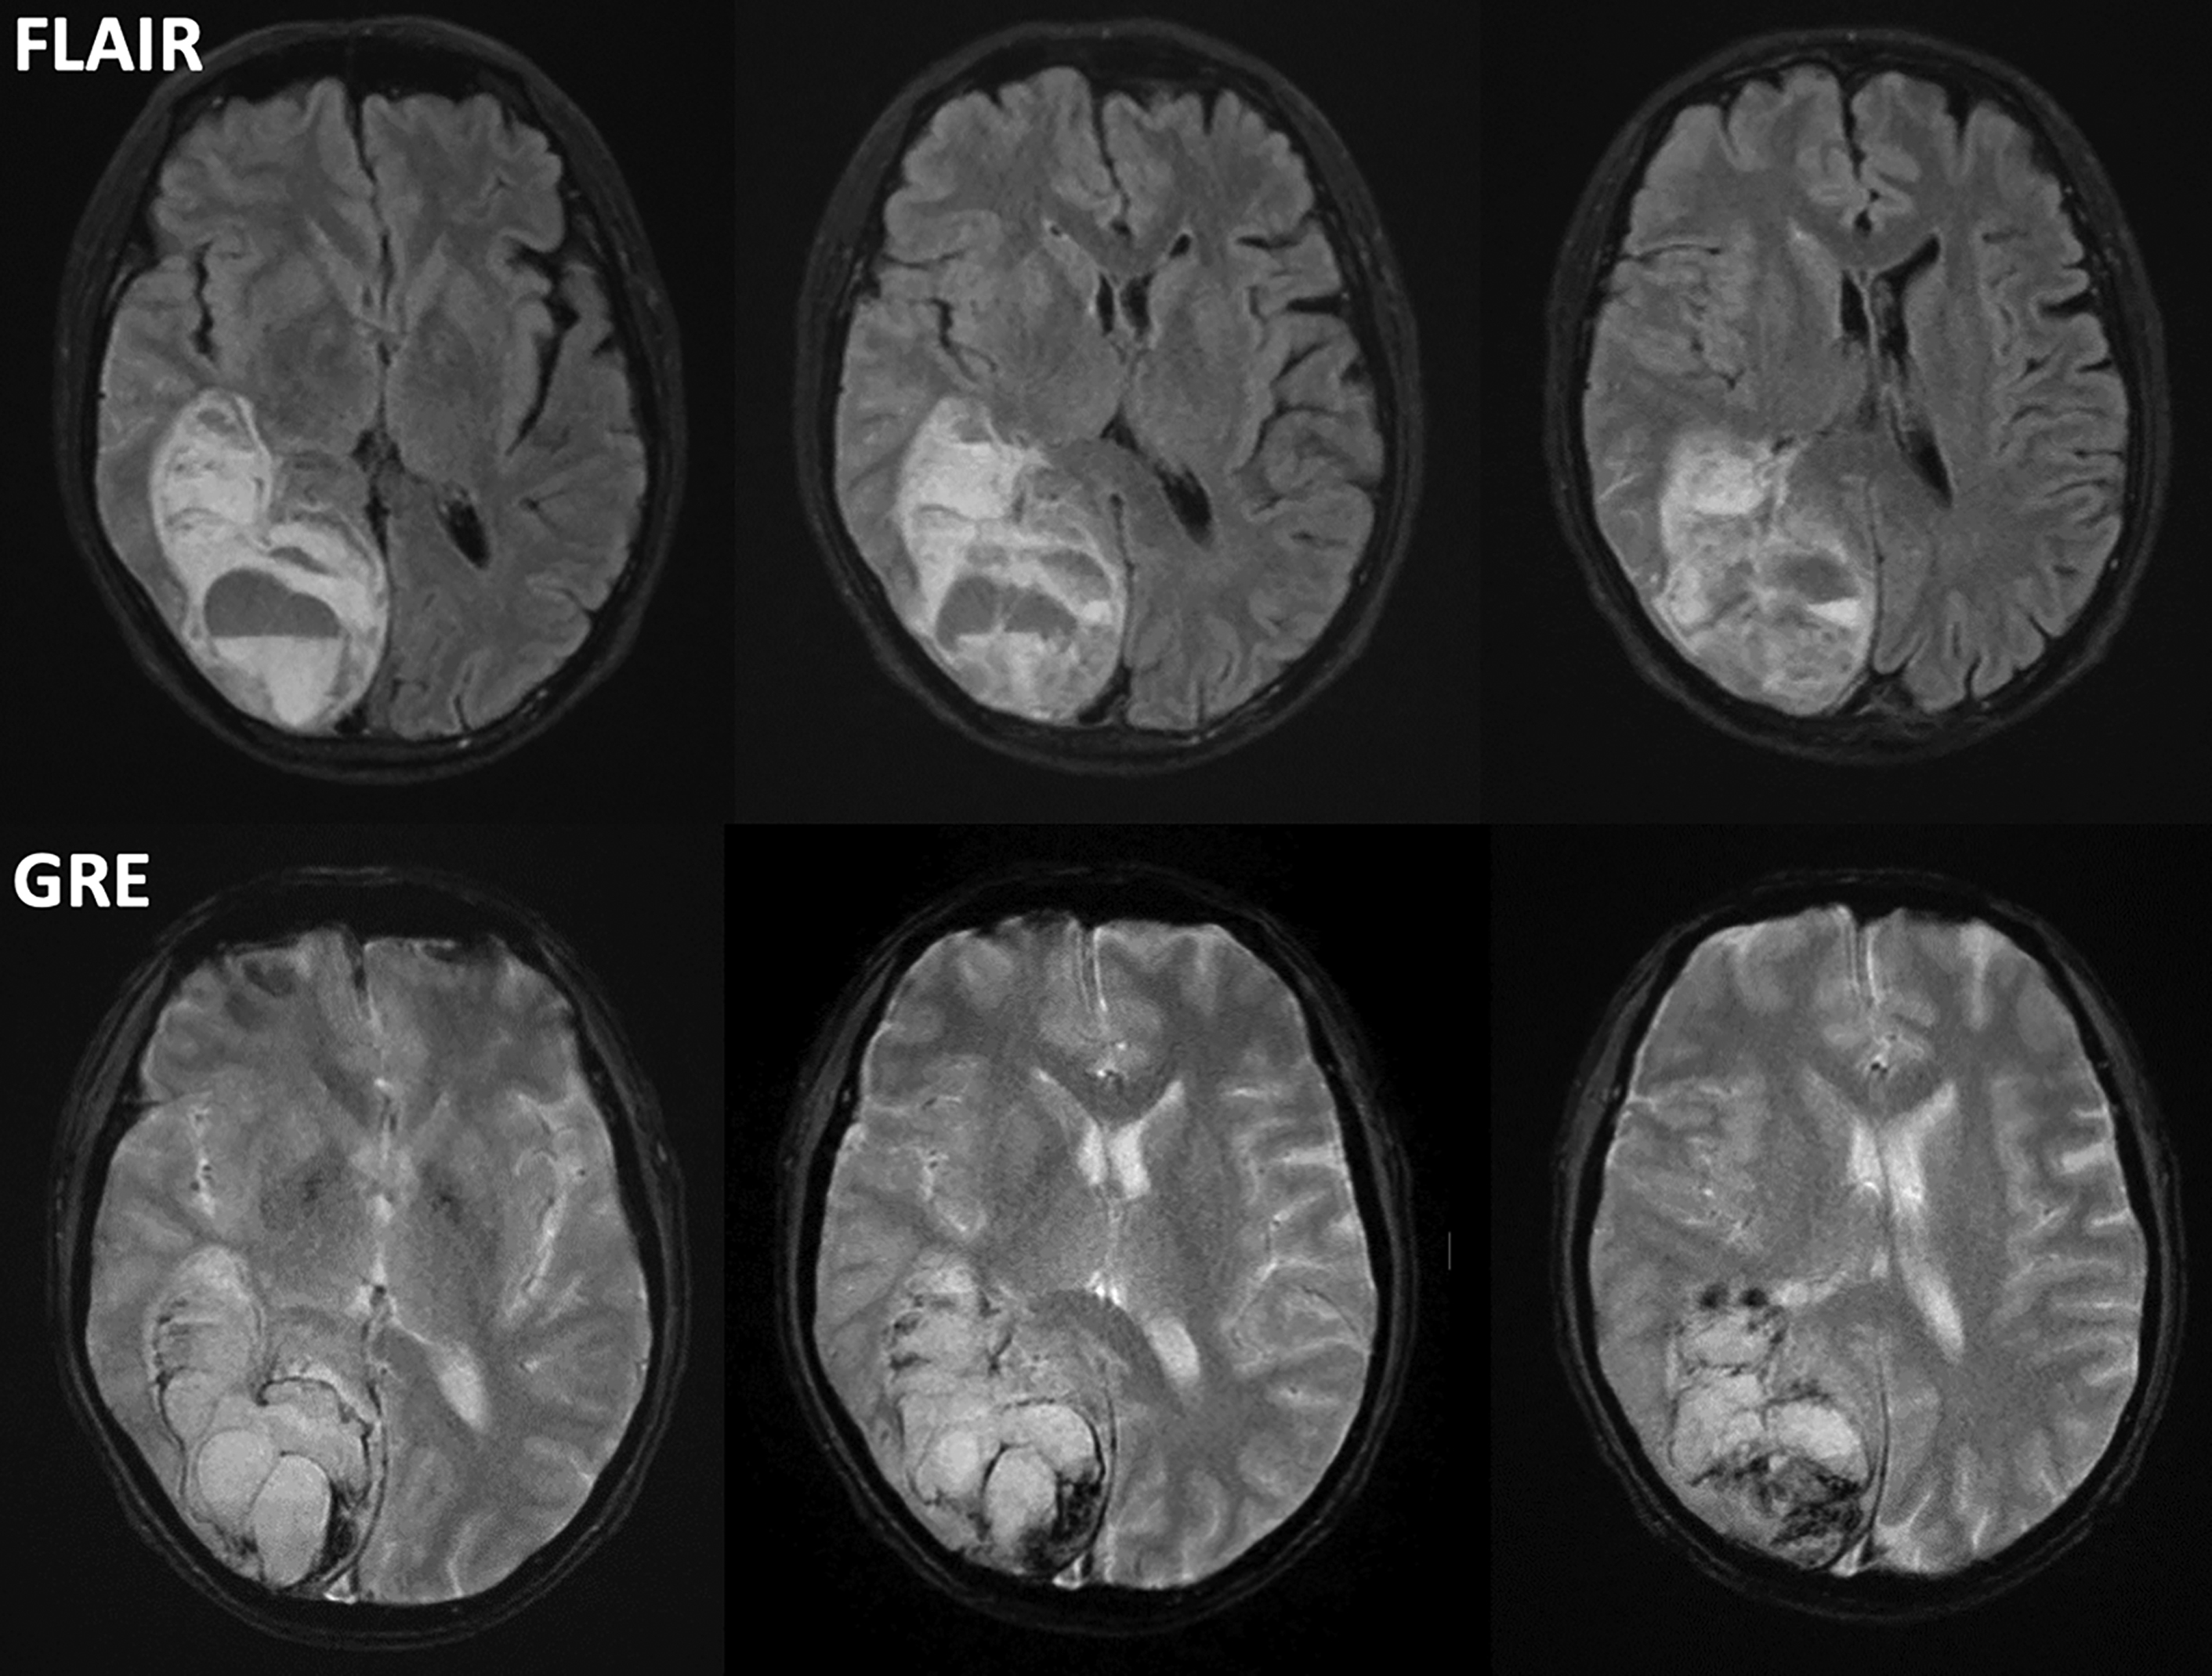

A Standardized MRI Stroke Protocol Stroke Old Stroke Radiology Ncct findings in ischemic stroke depend on the age of infarction: In this first article, we review various imaging modalities that are utilized to diagnose acute ischemic stroke. Hyperacute (less than 12 hours), acute (12 to 24 hours), subacute (24 hours to 5 days), and old (within weeks after stroke). The goal of imaging in a patient with acute stroke. Old Stroke Radiology.

Hemorrhagic Focus Within the Recent Small Subcortical Infarcts on Long Old Stroke Radiology The second part, appearing in the november/december 2021 issue. Exclude hemorrhage differentiate between irreversibly affected brain tissue and. Unenhanced ct can be performed quickly, can help identify early signs of stroke, and can help rule out hemorrhage. Use of various mr imaging sequences in dating ischemic stroke is discussed, with a brief review of the current and most widely accepted. Old Stroke Radiology.

Imaging Stroke Patients with Unclear Onset Times Radiology Key Old Stroke Radiology Hyperacute (less than 12 hours), acute (12 to 24 hours), subacute (24 hours to 5 days), and old (within weeks after stroke). In this first article, we review various imaging modalities that are utilized to diagnose acute ischemic stroke. The second part, appearing in the november/december 2021 issue. Use of various mr imaging sequences in dating ischemic stroke is discussed,. Old Stroke Radiology.